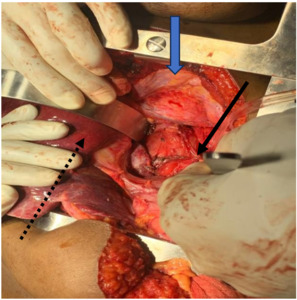

The mass was well circumscribed with moderate peritumoral fibrosis, and was located in the posterior mediastinum and upper retroperitoneum with adhesion to the right crus of the diaphragm, and adhesion and leftward displacement of the distal thoracic and abdominal esophagus. It abutted the hepatic veins and inferior vena cava. There was no evidence of invasion of the esophagus, proximal stomach, liver, thoracic or lumbar vertebrae (Figures 2a and 2b). There were no intra-thoracic or peritoneal metastases.

The right pleura was widely opened, the inferior pulmonary ligament divided, the lung retracted superiorly, and the diaphragmatic incision extended to expose the intra- abdominal component of the mass. The lower thoracic esophagus above the tumor was encircled and retracted towards to the patient’s left to expose the mass which was gradually dissected circumferentially, freed from the crura, esophagus, spine, hepatic veins, inferior vena cava, and descending thoracic aorta, and completely removed. The incision was closed in the standard manner with interrupted non-absorbable horizontal mattress sutures to reapproximate the diaphragm, and closure in layers of the thoracic and abdominal components of the incision.